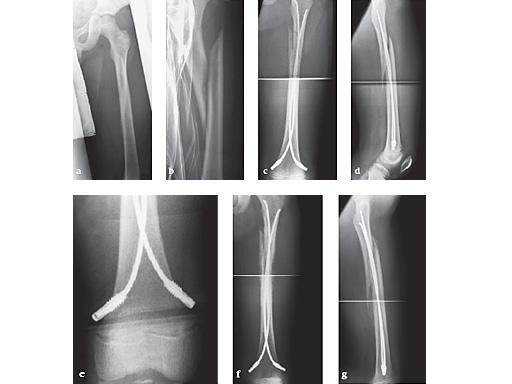

6-year-old girl, ski injury.

ab

X-rays show a long spiral fracture of the proximal third of the right femur (32D/5.1). Because of the age good indication for ESIN, but some danger of instability is possible.

cd

Postoperative x-rays. A closed reduction and fixation with 3.0 mm TEN was carried out with correct child-oriented alignment. For stability reasons two End Caps became uses. No signs of a shortening can be seen.

ef

AP and lateral view 6 weeks after surgery shows good callus formation and still a perfect alignment.

Full weight bearing was then allowed.

12-year-old boy; snow-board injury long spiral proximal femoral fracture (32D/5.1) primary indication for operation with ESIN and End Cap.

Injury x-rays.

Postoperative x-rays show a correct alignment and length. Fixation with 3.5 mm TEN and End Caps was performed.

e

This detail view shows the correct positioning of the End Caps.

fg

4 1/2 weeks postoperative a good callus and correct alignment was visible, full weight bearing was allowed.